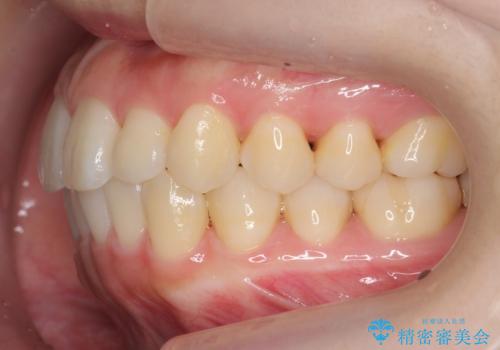

インビザライン モニターで前歯をきれいに

- 前歯のがたつきをきにされていました。

上下の前歯をやすりがけする処置(IPR)を行い、前歯の並びを出っ歯にしないようにしながら整えました。

症状が軽度であるためモニター採用になりました。